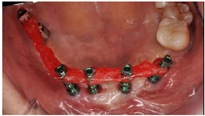

专科检查:双侧颧骨、下颌角过大,面中部凹陷。上唇唇正中可见术后瘢痕,红唇菲薄、唇珠消失(图1)。恒牙列,16-25缺失,17近中牙根外露,I°松动,26牙近中牙冠缺损。患者缺牙区牙槽突不平整,前庭沟变浅,水平向、垂直向咬合关系丧失(图2)。

正颌术后半年颌骨愈合良好,上下颌骨骨性反he(牙合)得到纠正,术后影像学显示右侧上颌窦嵴距骨高度不足,17牙临床牙冠伸长且伴松动,前牙区骨量充足,但缺牙区前庭沟变浅伴有角化黏膜量缺损。为减小手术创伤、缩短治疗周期并能够达到长期稳定的治疗效果,设计在前牙区倾斜植入带有光滑颈圈的拓美超亲水种植体,根据植入位点设计并制作2副牙支持式种植手术导板。局部浸润麻醉,牙槽顶黏骨膜切口,翻瓣显露牙槽嵴顶,戴入双侧后牙支持的第一副前牙区种植手术导板(图8.1),逐级备孔,前牙区植入4颗ø4.0*8 mm拓美种植体,初期稳定性均>30Ncm(图8.2)。拔除17、18患牙,戴入左侧后牙支持的第二副种植手术导板(图8.3),17牙位点逐级备孔并植入1颗ø5.0*12 mm拓美种植体,初期稳定性20Ncm,跳跃间隙内植入自体骨屑,所有种植体均埋入式愈合,对位缝合黏骨膜。

种植体周围角化黏膜厚度不足可导致牙槽嵴边缘骨吸收,增加种植体周围疾病的发病风险,不利于种植体周围组织健康。目前研究认为采用软组织移植术等方式可有效增加种植体周围角化黏膜厚度,改善种植体周围软组织健康状况,提高种植成功率。由于颌骨创伤和骨折术后感染、多次手术等因素,上颌缺牙区种植体唇侧角化黏膜不足2mm,上唇唇珠丧失(图9)。设计在种植体达到骨结合时,制备双侧硬腭角化黏膜游离移植增宽种植体唇侧角化黏膜量,重建患者上颌前庭沟。手术设计上颌前牙种植区牙槽嵴顶黏膜切口,骨膜上向唇侧钝性分离至前庭沟底,将唇侧游离黏膜与前庭沟底骨膜缝合固定,显露受区创面。为减轻术后供区疼痛不适故保骨膜上制取双侧上颌第二磨牙至尖牙对应腭侧角化黏膜,将其植入受区骨膜上(图9.1)。同期,应用自体脂肪充填术纠正外伤术后唇红畸形(图9.4)。术后2个月可见愈合基台唇侧角化黏膜宽度显著增加(图9.2)。